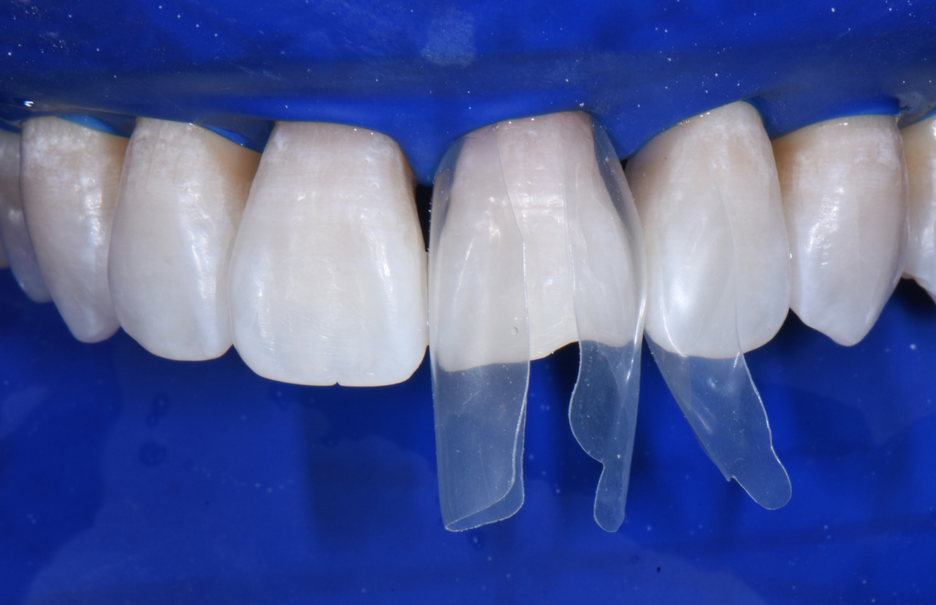

Revolutionary Bioclear Black Triangle Treatment Smile Cliniq

From www.smilecliniq.com

Revolutionary Bioclear Black Triangle Treatment Smile Cliniq Treatment For Black Triangles Web talk to your dentist if you notice black triangles between your teeth. Web gingival black triangles (gbts) are generally considered to be aesthetically unacceptable, have a multifactorial aetiology. We explain what these dark triangles mean, how to treat. Typically, each gap between someone’s teeth is filled with a little bit of gum tissue, called a papilla. The options for. Treatment For Black Triangles.